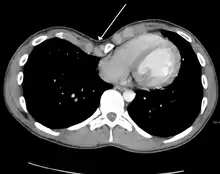

Pectus excavatum is initially suspected from visual examination of the anterior chest. Auscultation of the chest can reveal displaced heart beat and valve prolapse. There can be a heart murmur occurring during systole caused by proximity between the sternum and the pulmonary artery.[15] Lung sounds are usually clear yet diminished due to decreased base lung capacity.[16]

Many scales have been developed to determine the degree of deformity in the chest wall. Most of these are variants on the distance between the sternum and the spine. One such index is the Backer ratio which grades severity of deformity based on the ratio between the diameter of the vertebral body nearest to xiphosternal junction and the distance between the xiphosternal junction and the nearest vertebral body.[17] More recently the Haller index has been used based on CT scan measurements. An index over 3.25 is often defined as severe.[18] The Haller index is the ratio between the horizontal distance of the inside of the ribcage and the shortest distance between the vertebrae and sternum.[19]

Chest x-rays are also useful in the diagnosis. The chest x-ray in pectus excavatum can show an opacity in the right lung area that can be mistaken for an infiltrate (such as that seen with pneumonia).[20] Some studies also suggest that the Haller index can be calculated based on chest x-ray as opposed to CT scanning in individuals who have no limitation in their function.[21]